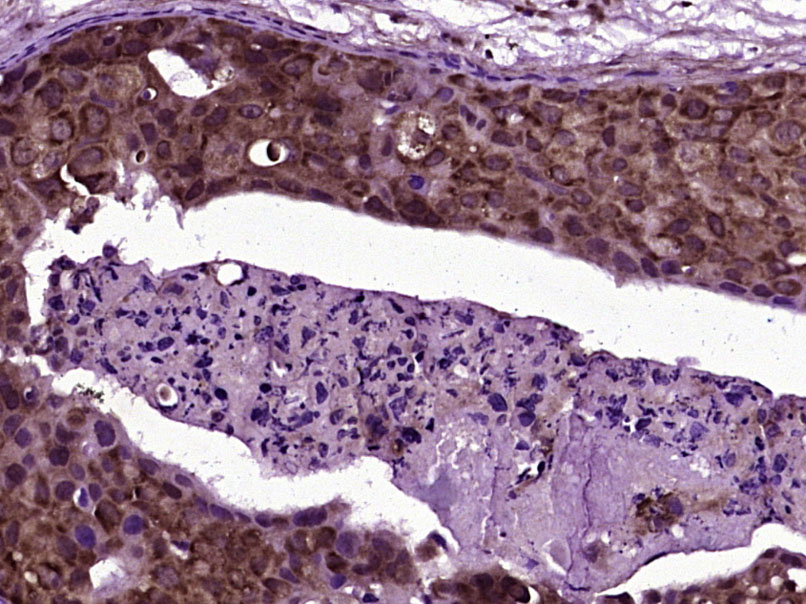

| 产品应用 | IHC-P=1:100-500, IHC-F=1:100-500, IF=1:100-500 Not yet tested in other applications. |

| {IHC-P} | {1:100-500} |

| {IHC-F} | {1:100-500} |

| {IF} | {1:100-500} |